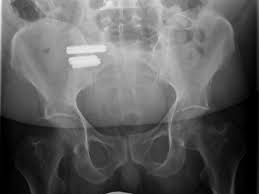

Aus funktioneller Sicht unterscheidet man zwischen einer Beckenverwringung und einer ISG-Blockade Die Beckenverwringung ist eigentlich ein normaler Prozess beim Gehen. Meist verlaufen sie einseitig aber behindern uns dennoch in der Gesamt-Beweglichkeit. Das Kreuzdarmbeingelenk wird auch als Iliosakralgelenk oder ISG bezeichnet.

Es hat sehr lange gedauert bis das behandelt wurde ich habe es erst verschleppt und dann wurde ich über Jahre nicht ernstgenommen beim Arzt sodass die Problematik mittlerweile. Ilio-Sacral-Gelenk-Block vorliegt eine Blockade des Kreuzbein-Beckenschaufel-Gelenks rechts oder links welche ebenfalls zu einer Verspannung des Beckenbodens führen kann. Das ISG auf der rechten Seite ist über einen Punkt mit dem Dünndarm verbunden.

Schwimmen bei akuten isg Schmerzen. Die ISG-Blockade verursacht sowohl ISG-Schmerzen der betroffenen Seite als auch Schmerzen die aus dem unteren Rücken über das Gesäß den hinteren Oberschenkel entlang bis zum Knie ausstrahlen können.